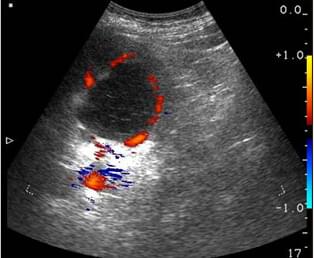

- Naravno. Prvi slučaj je povezan sa kamenjem u bubrezima. Javio mi se muškarac od 27 godina sa

bolovima na desnoj strani

koji su počinjali kod grudi i završavali se negde u predelu mokraćne bešike. Bolovi su se

manifestovali kratkim grčevima, konvulzijama, hladnim znojem i javljali su se u valovima.

Snimak je pokazao prisustvo kamena od 19 mm koji je zapeo u gornjem delu bubrega. Za topljenje

kamena u bubregu propisali smo

Nefro Aktiv

.

Za dva dana nakon početka upotrebe, kamen je počeo da se razbija i potpuno je izašao za jednu

nedelju. Pri tome pacijent nije osećao nikakve neprijatnosti.

pre

pre

posle

posle